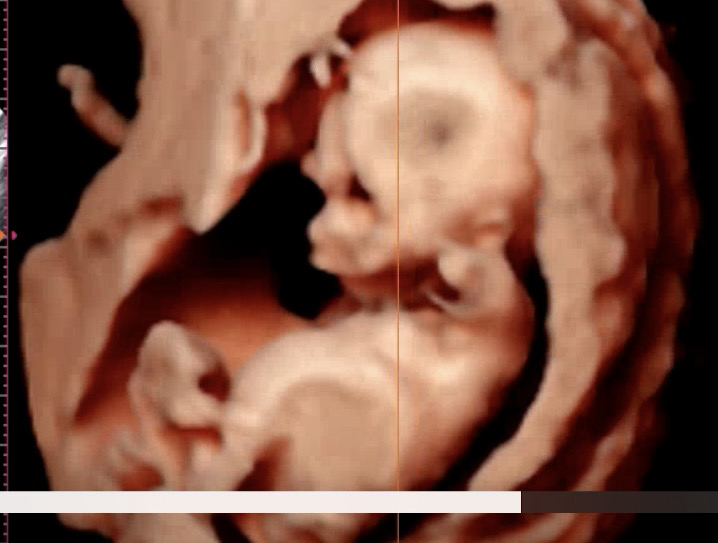

눈이 왜이래요? ㅠㅠ

ㅠㅠ

제 애기도 아직은 얼굴이 베놈 같이 생겼더라구요

아직 뼈바께 없어서그래요..